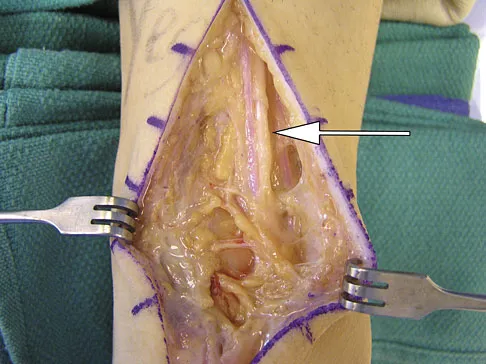

A 51-year-old male truck driver has had progressive left hip pain for more than 2 years, and he reports that the pain has become severe in the past 9 months. He is now unable to work because of the pain. Examination reveals that range of motion of the hip is limited to 95 degrees of flexion, 0 degrees of internal rotation, and 20 degrees of external rotation. The plain radiograph, MRI scan, and intraoperative gross photographs are shown in Figures 9a through 9d. Management should consist of